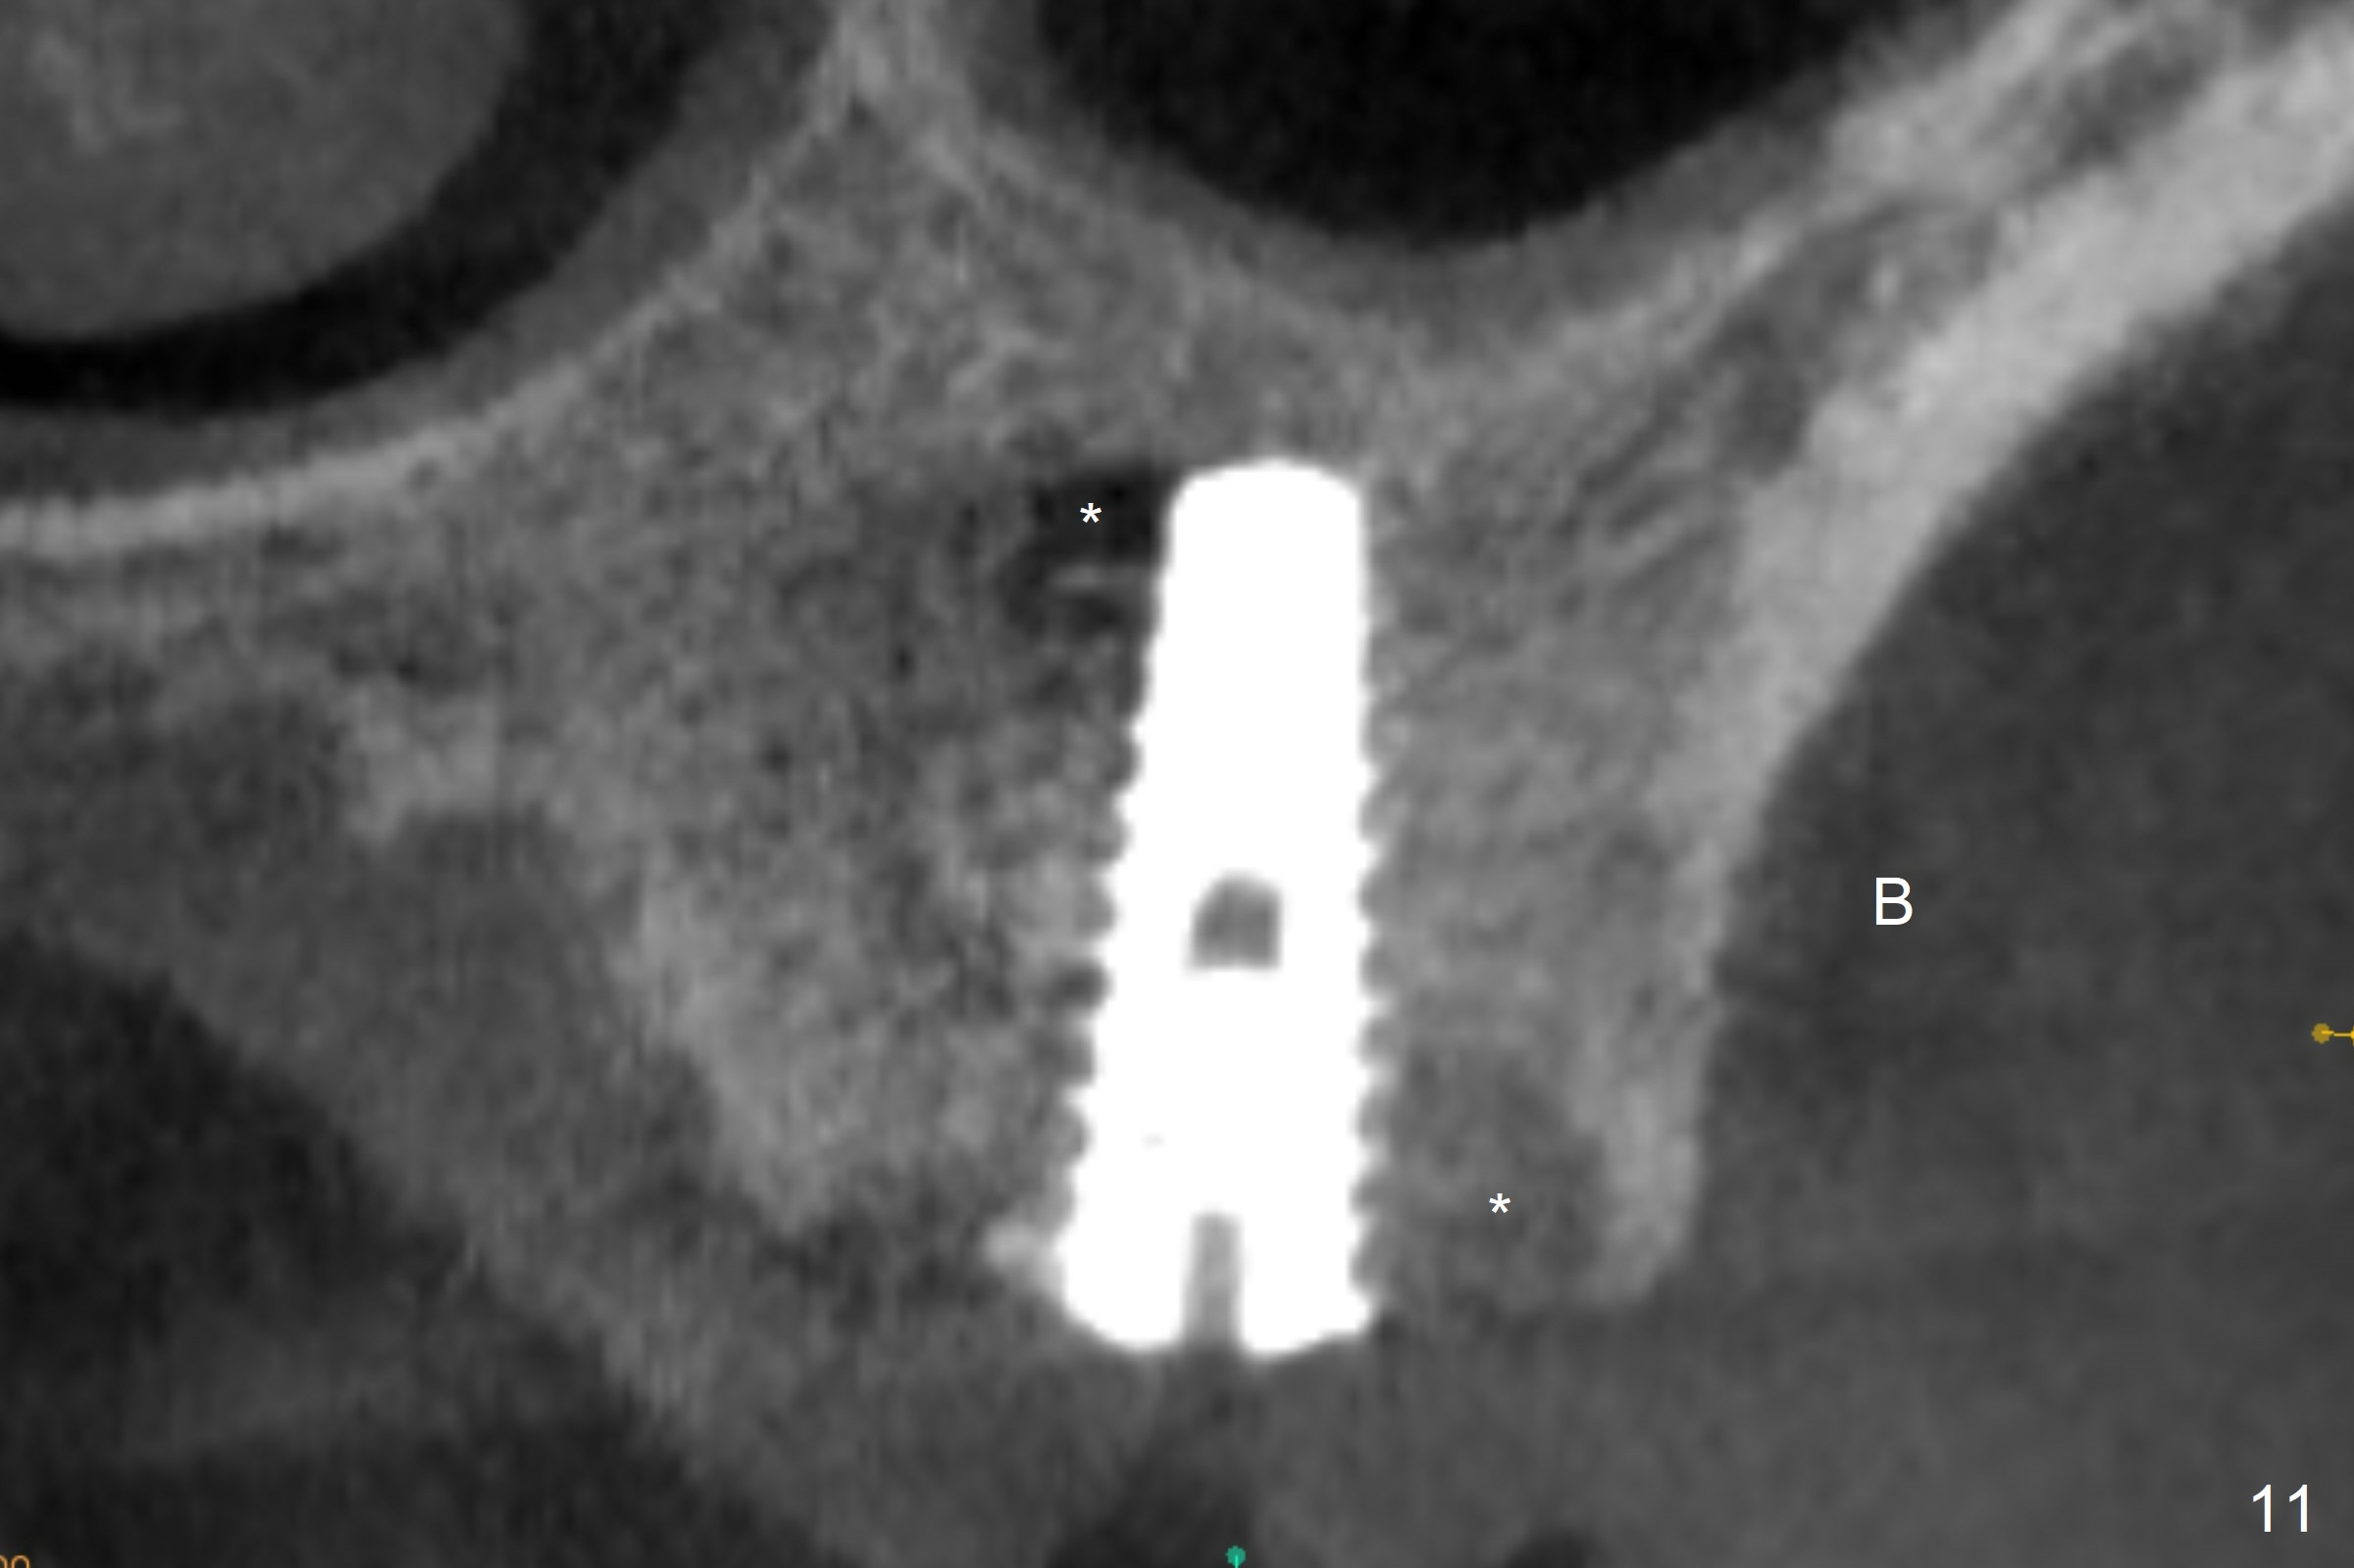

The amount of the bone graft mesial and distal the implant seems to reduce 3 and 4 months postop, respectively (Fig.6,7 arrowheads). When the acrylic is cut off 4 months postop, the bone graft is loose. The gingiva is unhealthy. The abutment and implant are loose. A healing abutment is placed (5x4 mm). The implant is torqued to 35 Ncm 6 months postop with the healing abutment reapplied. The patient will return for follow up nearly 9 months postop. A larger healing abutment will be used if the implant is stable. Two weeks later, use a smaller restorative abutment for easy impression. In fact the implant is unstable with #15 mesial shift due to abnormal occlusion with #17 (Fig.8). Bone density around the implant is low (* in Fig.9 (PA), 10,11 (CT sagittal, coronal sections)). A healing screw is placed for self healing. A 2nd option is to remove the implant (Fig.12), BEB (Fig.13) and place the implant deeper (Fig.14) or larger one (5.5-6.5x13 mm). The 3rd option is to place larger and longer implants (Fig.15 (tapered), 16 (cylindrical)). The implant access has partially closed 14 months postop, but there is a small buccal opening with sanguine exudate. Incision reveals severe bone loss around the implant; the mobile tooth #15 is extracted (Fig.17). After debridement and irrigation with normal saline, Vera Graft (Fig.18 *) and Collagen plug are placed with periodontal dressing.